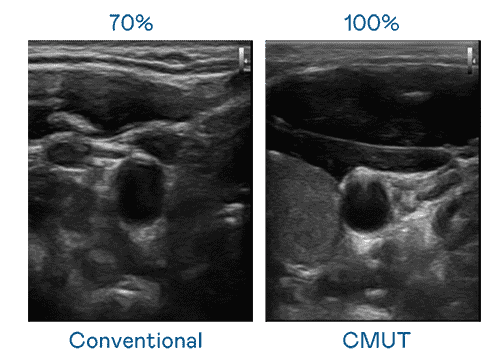

CMUT 技术是一种用电容式微机电元件来产生超音波讯号的技术。。。。与传统 PZT 压电式技术相比,,,CMUT 频宽增加 30%,,,更宽频的超音波讯号让影像解析度大幅提升,,,,是实现高影像品质医疗超音波扫描、、促进精准医疗发展的关键技术。。。

大频宽带来超清晰影像

超音波影像的解析度高低,,,,首先取决于探头能发出的讯号频宽。。。。人生就是博 CMUT 可提供高清晰的超音波讯号,,提供高频宽、、、高灵敏度、、、、影像纹理细节更高的超音波影像,,协助医护人员缩短影像判读时间及利用精准的医疗影像进行诊断。。